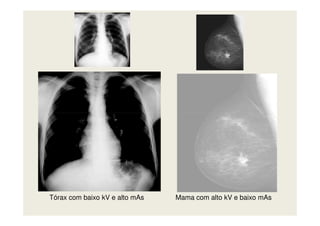

Técnica de Alto Contraste

Baixo kV / Alto mAs

Técnica de Baixo Contraste

Alto kV / Baixo mAs

Tórax com baixo kV e alto mAs Mama com alto kV e baixo mAs

Contraste radiográfico Estruturas comdensidades muito diferentes Estruturas com densidades muito próximas ALTO kV = BAIXO contraste BAIXO kV = ALTO contraste Técnica de Alto Contraste Baixo kV / Alto mAs Técnica de Baixo Contraste Alto kV / Baixo mAs

Tórax com baixokV e alto mAs Mama com alto kV e baixo mAs